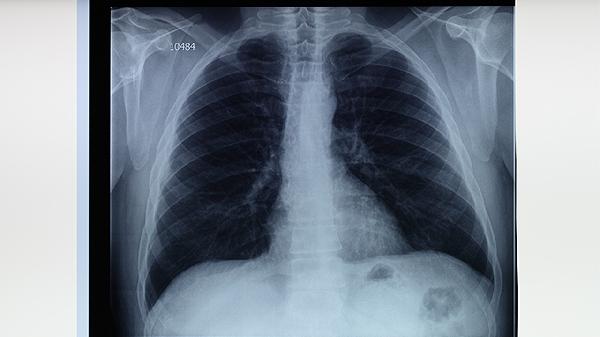

肺结核筛查出现过敏反应怎么回事,怎么办

肺结核筛查出现过敏反应可能与筛查试剂成分过敏、皮肤敏感、操作不当、免疫系统异常或既往过敏史等因素有关。过敏反应通常表现为局部红肿、瘙痒、皮疹等症状,可通过停用筛查试剂、局部冷敷、抗过敏药物等方式缓解。